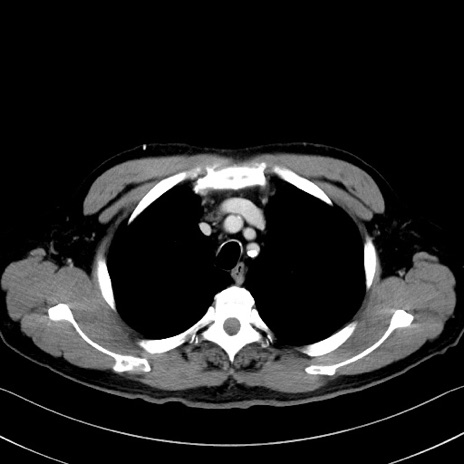

症例35(横断像)

【症例】70歳代 男性

【主訴】腹部膨満、嘔吐

【現病歴】昨日より腹部膨満感出現。本日増悪し、仙痛出現。嘔吐あり、受診。

【既往歴】糖尿病、胆摘後

【身体所見】BP 149/80mmHg、HR 74/min、BT 35.9℃、腹部:膨満、軟、圧痛なし。腸雑音減弱あり。上腹部正中切開瘢痕あり。

【データ】WBC 13500、CRP 1.72